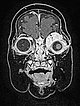

Die koronare, native T1-gewichtete MRT zeigt die Raumforderung homogen hypointens. Zentral einige wenige kleine flow-voids durch stark perfundierte arterielle Gefäße.